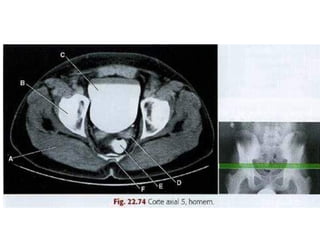

Varredura da Pelve

• Os limites são definidos pela extremidade

superior da crista ilíaca até a extremidade

inferior do ísquio.